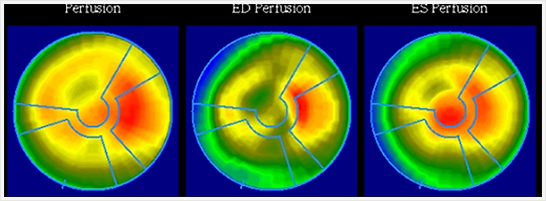

画像紹介

安静時心筋血流シンチグラフィ

心臓の筋肉に酸素や栄養を供給する冠動脈が狭窄または閉塞すると、心臓は虚血状態になり、心筋梗塞に陥ります。心筋細胞の状態(虚血部位、梗塞範囲)を調べる目的で行われる検査です。

6.健康な心臓の筋肉には通常良く集まり、障害がある場合はその障害の程度に応じた集積の低下がみられます。